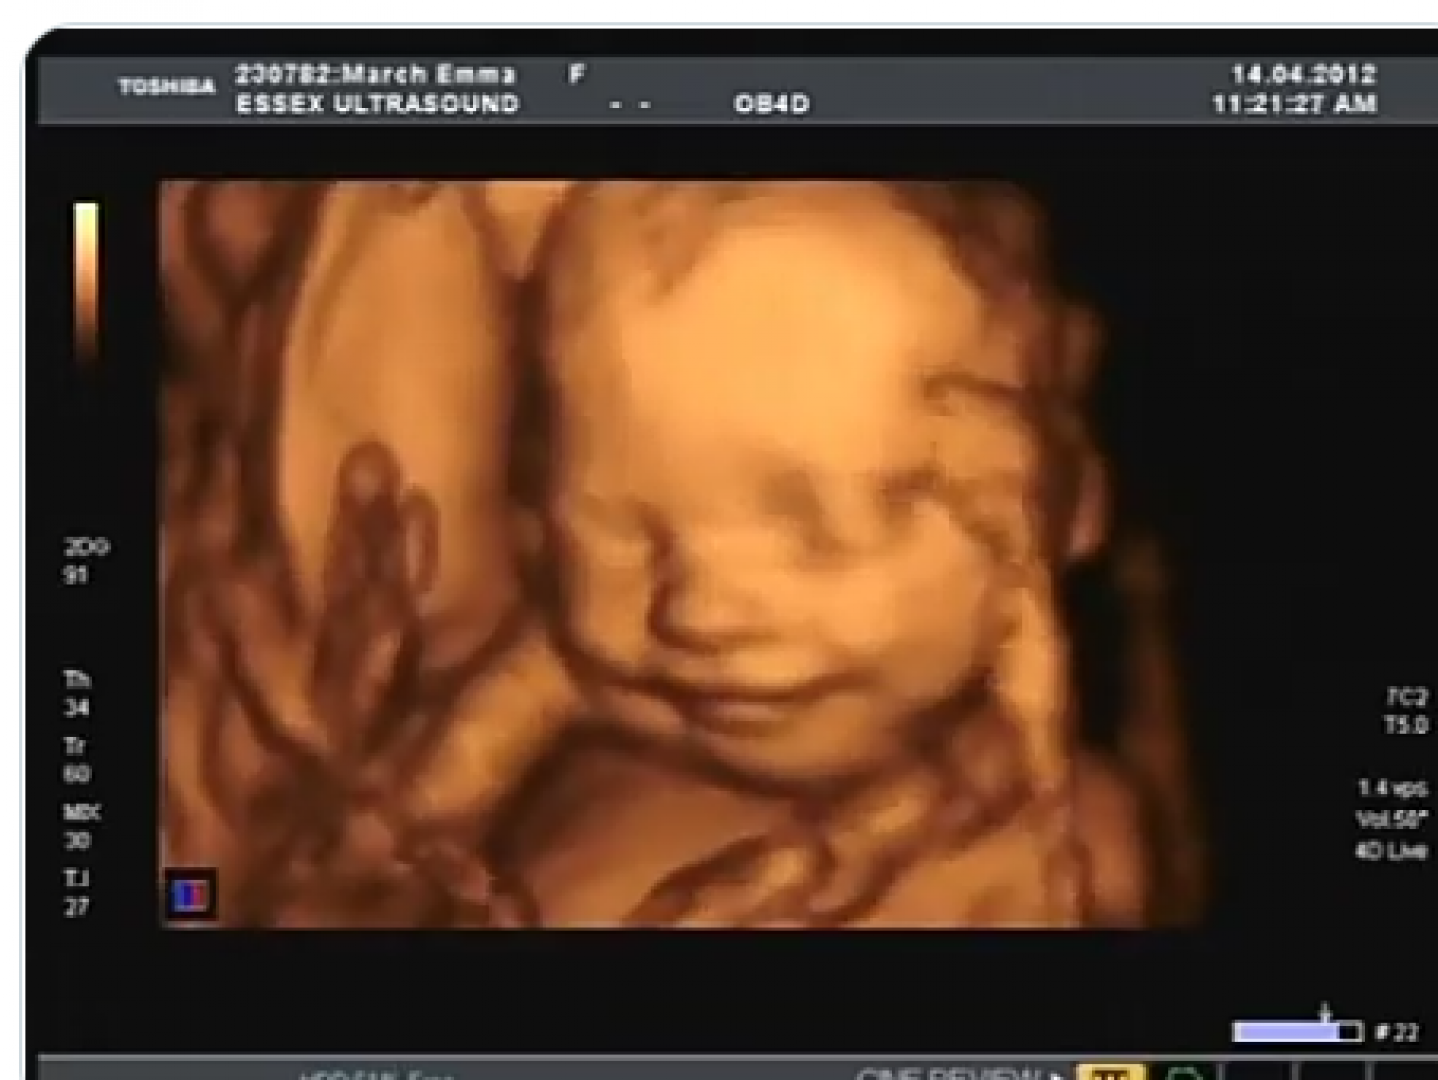

حركة الجنين من أهم العلامات التي تشير إلى صحة وسلامة الجنين بشكل عام، كما أن حركة الجنين في الشهر التاسع تقل من حيث الكثافة ولكنها تزداد من حيث القوة، مما يسبب الآلام الشديدة للأم لفترات طويلة.